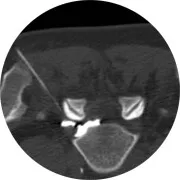

Le scanner (également appelé tomodensitométrie) est un examen qui explore la plupart des organes (cerveau, cœur, poumon, artères, foie, vésicule biliaire...) de façon précise, même au travers des os. En combinant des rayons X (comme la radiographie) à des supports informatiques puissants, il permet de réaliser des images du corps en coupes (ou « en tranches ») très fines. Une fois reconstruites par le biais d’un ordinateur, ces images permettent de visualiser les différents organes en trois dimensions.

Le scanner se présente comme un anneau (environ 2 m de diamètre) sous lequel coulisse une table d’examen où le patient est allongé. À l’intérieur de cet anneau se trouve un tube à rayons X qui tourne autour du patient pendant toute la durée de l’examen.